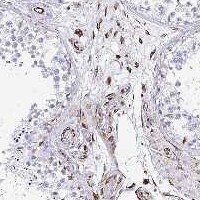

Supportive validation

- Submitted by

- Invitrogen Antibodies (provider)

- Main image

- Experimental details

- Immunohistochemistry analysis of TMEM54 in human testis. Samples were incubated with TMEM54 polyclonal antibody (Product # PA5-144891). Shows strong positivity in endothelial cells.